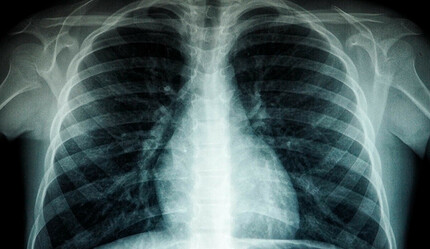

Tıptaki adıyla tüberküloz olarak da bilinen verem, hava yoluyla bulaşan bir akciğer hastalığı. Mycobacterium Tuberculosis adlı bakterinin yol açtığı hastalık tedavi edilmediği durumda ölümcül olabilir.